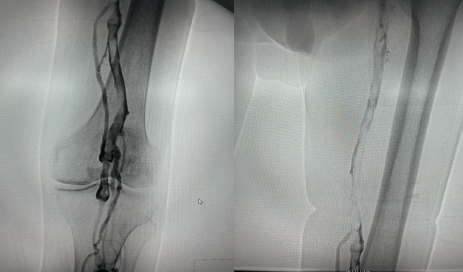

留置接觸性溶栓導(dǎo)管并微量泵人尿激酶溶栓(50萬U/日),小劑量溶栓既降低溶栓出血風(fēng)險、又保證了療效;溶栓72小時后,拔除溶栓導(dǎo)管,復(fù)查造影左下肢深靜脈血流通暢,血栓全部消失,達(dá)到預(yù)期效果。

復(fù)查造影左下肢深靜脈血流通暢,血栓完全消失